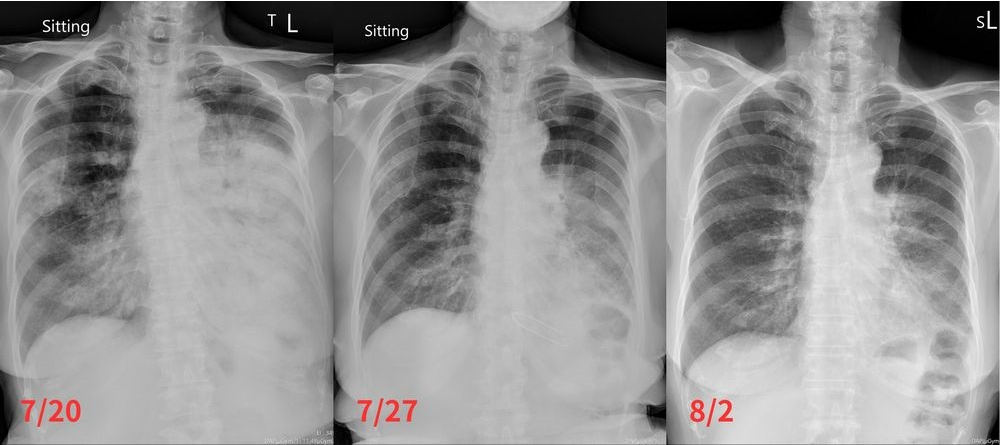

▲方奶奶於七月下旬轉往花蓮慈院時,X光影像顯示肺部有明顯陰影,經標靶藥物治療五天後已減少許多,治療二週後更僅剩肺葉的一點陰影。

因醫師快速的診斷和標靶藥物針對性的治療,方奶奶在投入藥物五天內,肺部陰影就明顯減少,治療二週後的X光影像更是僅剩下肺葉的一點陰影,常咳及多痰症狀也大大改善。林智斌主任表示,臨床上偶爾會遇到類似的不典型肺癌患者,因疾病表現不尋常,尤其需仰賴醫師的經驗,靈活從其他切入點診治。若治療方案無效,病人狀況可能會持續惡化,甚至威脅生命健康;所幸及時治療得當,目前方奶奶病情已趨於穩定,按時服藥控制中。

「從X光片及電腦斷層(CT)來看,怎麼看都像是肺炎。」林智斌主任表示,久咳不止和痰量大,加上CT影像看到實質化(Consolidation)及空氣支氣管徵象(Air Bronchogram),方奶奶的疾病表現是很典型的肺炎,只是經過抗生素治療一個月,病人的情況卻沒有好轉,反而越來越嚴重,勢必要調整治療方針。過去的臨床經驗讓他果斷地建議病人做切片檢查,隔日病理結果確定為肺腺癌第四期,立刻安排病人進行基因檢測,以尋找適合的標靶藥物,並於結果出來後盡速投入藥物治療。

▲病人症狀表現及影像檢查結果是很典型的肺炎,但經抗生素治療無好轉,花蓮慈院胸腔內科主任林智斌果斷建議做切片檢查,後續確定為肺腺癌。